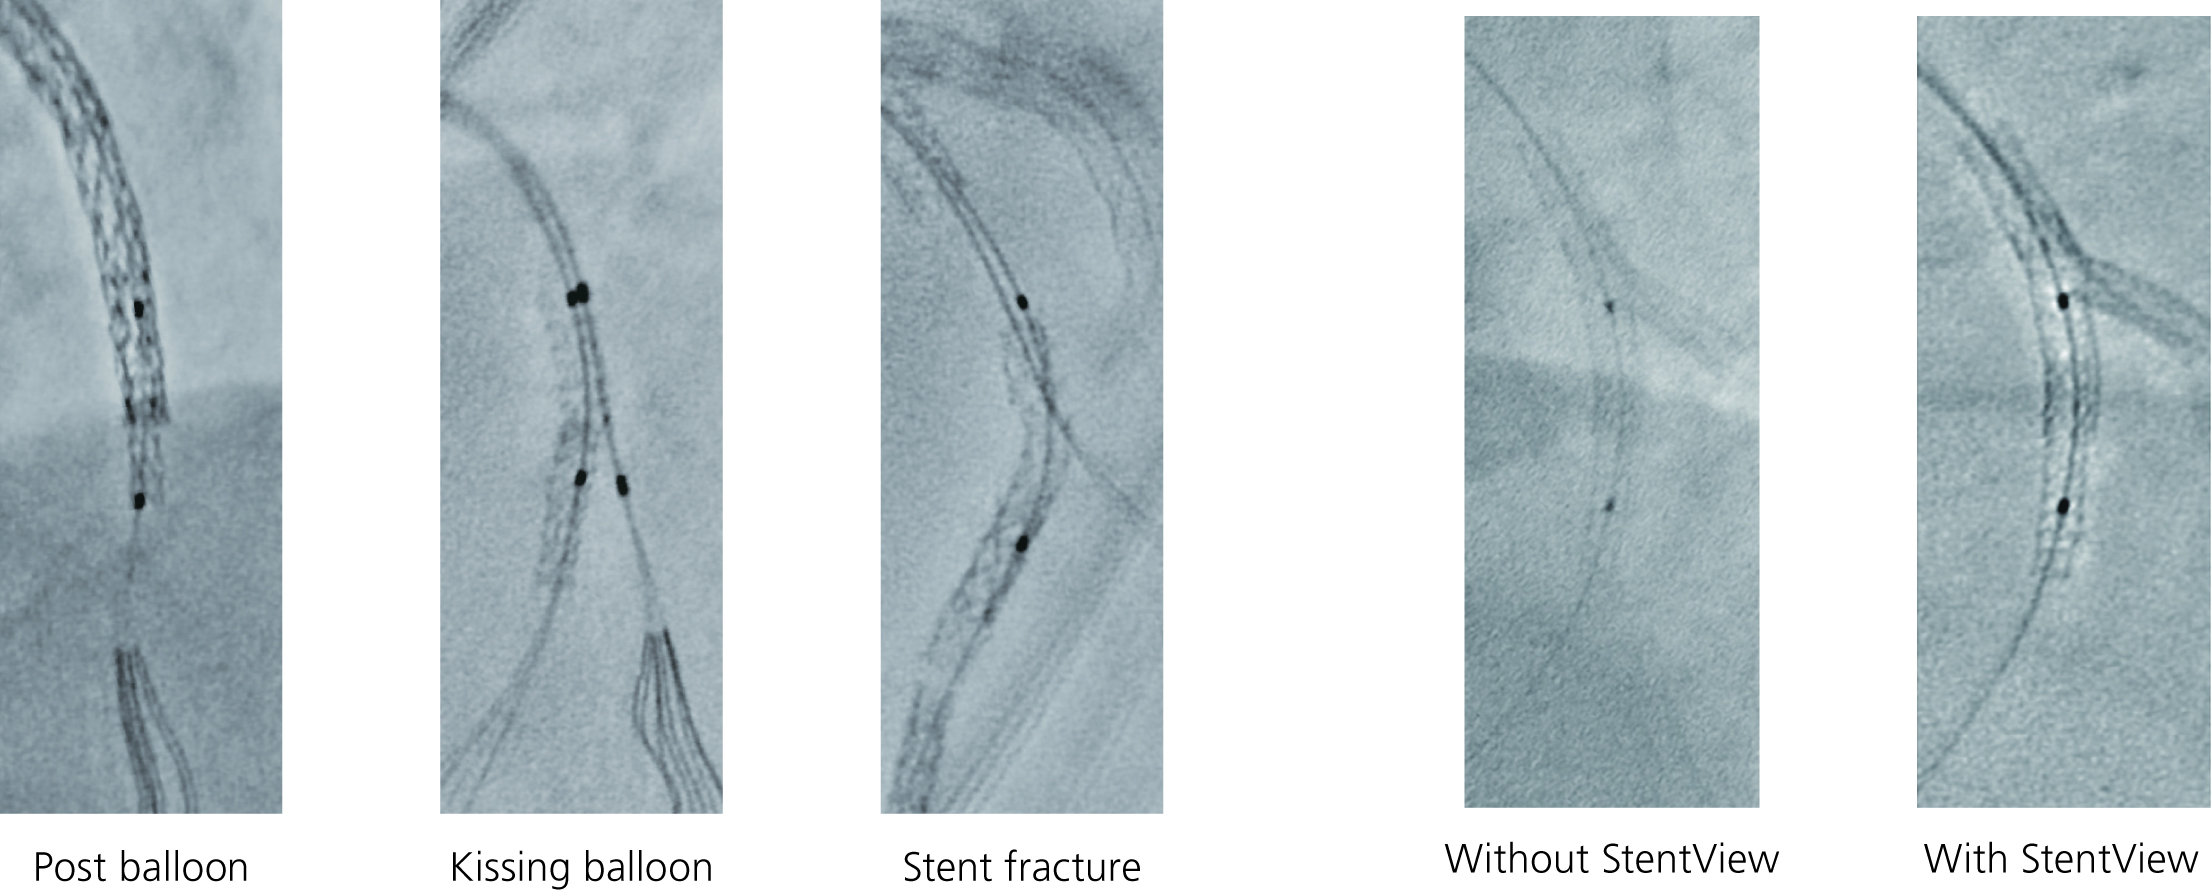

实时支架增强显影(StentView+Plus)是开云手机登录入口·(中国)官方网站公司开发的一种独特成像技术,它基于实时图像处理技术,很好地支持PCI手术。在通常的PCI手术中,支架随着心脏的搏动而移动,采用实时支架增强显影(StentView+Plus)之后,可以把支架影像固定下来,以便医生更仔细地观察,而这一过程完全是实时的,而非后处理的图像。这对于评估重叠支架之间的位置关系,或者当使用气囊进行再扩张支架时特别有效。

该功能可以定义多个感兴趣区(ROI),并且可以自动检测球囊标记点,使得检测效率提高,减少整体检查时间。